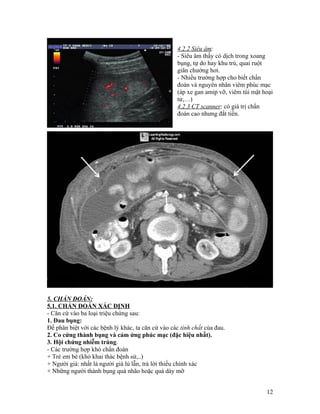

4.2.2 Siêu âm:

- Siêu âm thấy có dịch trong xoang

bụng, tự do hay khu trú, quai ruột

giãn chướng hơi.

- Nhiều trường hợp cho biết chẩn

đoán và nguyên nhân viêm phúc mạc

(áp xe gan amip vỡ, viêm túi mật hoại

tử,…)

4.2.3 CT scanner: có giá trị chẩn

đoán cao nhưng đắt tiền.